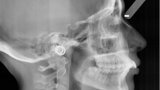

Distalizace horních molárů pomocí alignerů a cyklických sil